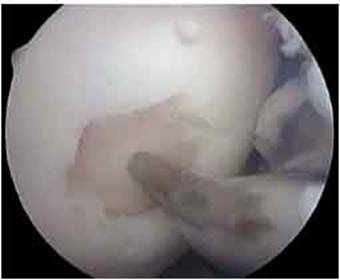

Fig.18. Secvente din timpul operatiei cu artroscopul